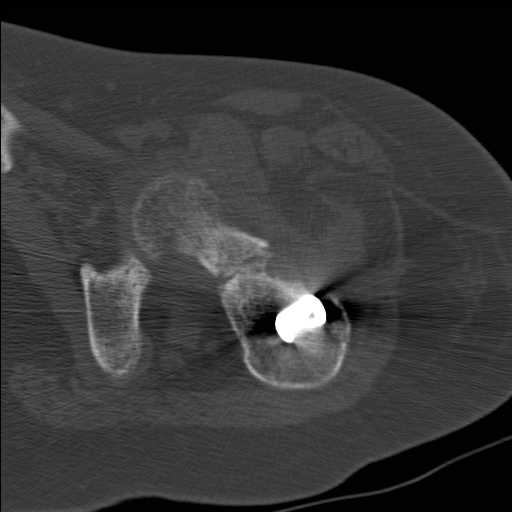

Добрый день уважаемые коллеги. Во такая ситуация. Девушка 19 лет травму получила в мае 2016г (изолированная травма, трансцервикальный перелом шейки левого бедра). Соматически здорова. Лечилась по месту жительства скелетным вытяжением в течении 1 месяца.

Затем переведена в наше учреждение. 18 июня выполнена операция, детали где , кто и как уточнять не имеет смысла( из протокола операции: выполнялась передняя артротомия, репозиция под визуальным контролем) . Учитывая характер выполненного остеосинтеза, после операции постельный режим 6 недель. Снимки в хронологии все выкладываю. КТ контроль сделан 2.09.16. для оценки состояния головки бедра. Помогите, определиться с дальнейшей тактикой.

согласен с Александром Николаевичем, надо пытаться сохранить сустав (в т.ч. его страдающее кровоснабжение. Судя по КТ Сохраняется ретроверсия шейки бедра. Вероятны трудности с репозицией последней. Для создания правильного направления шеечных винтов (Винта) возможно придется делать вальгусно-антекурвационную межвертельную остетомию, тем самым произвести разгибание в т/бедренном суставе проксимального отломка. И ретроверсия станет в большей степени вальгусом. То есть точка входа для гвоздя должна быть кзади от торчащей части прорезавшегося клинка со всеми вытекающими перемещениями проксимальной части.